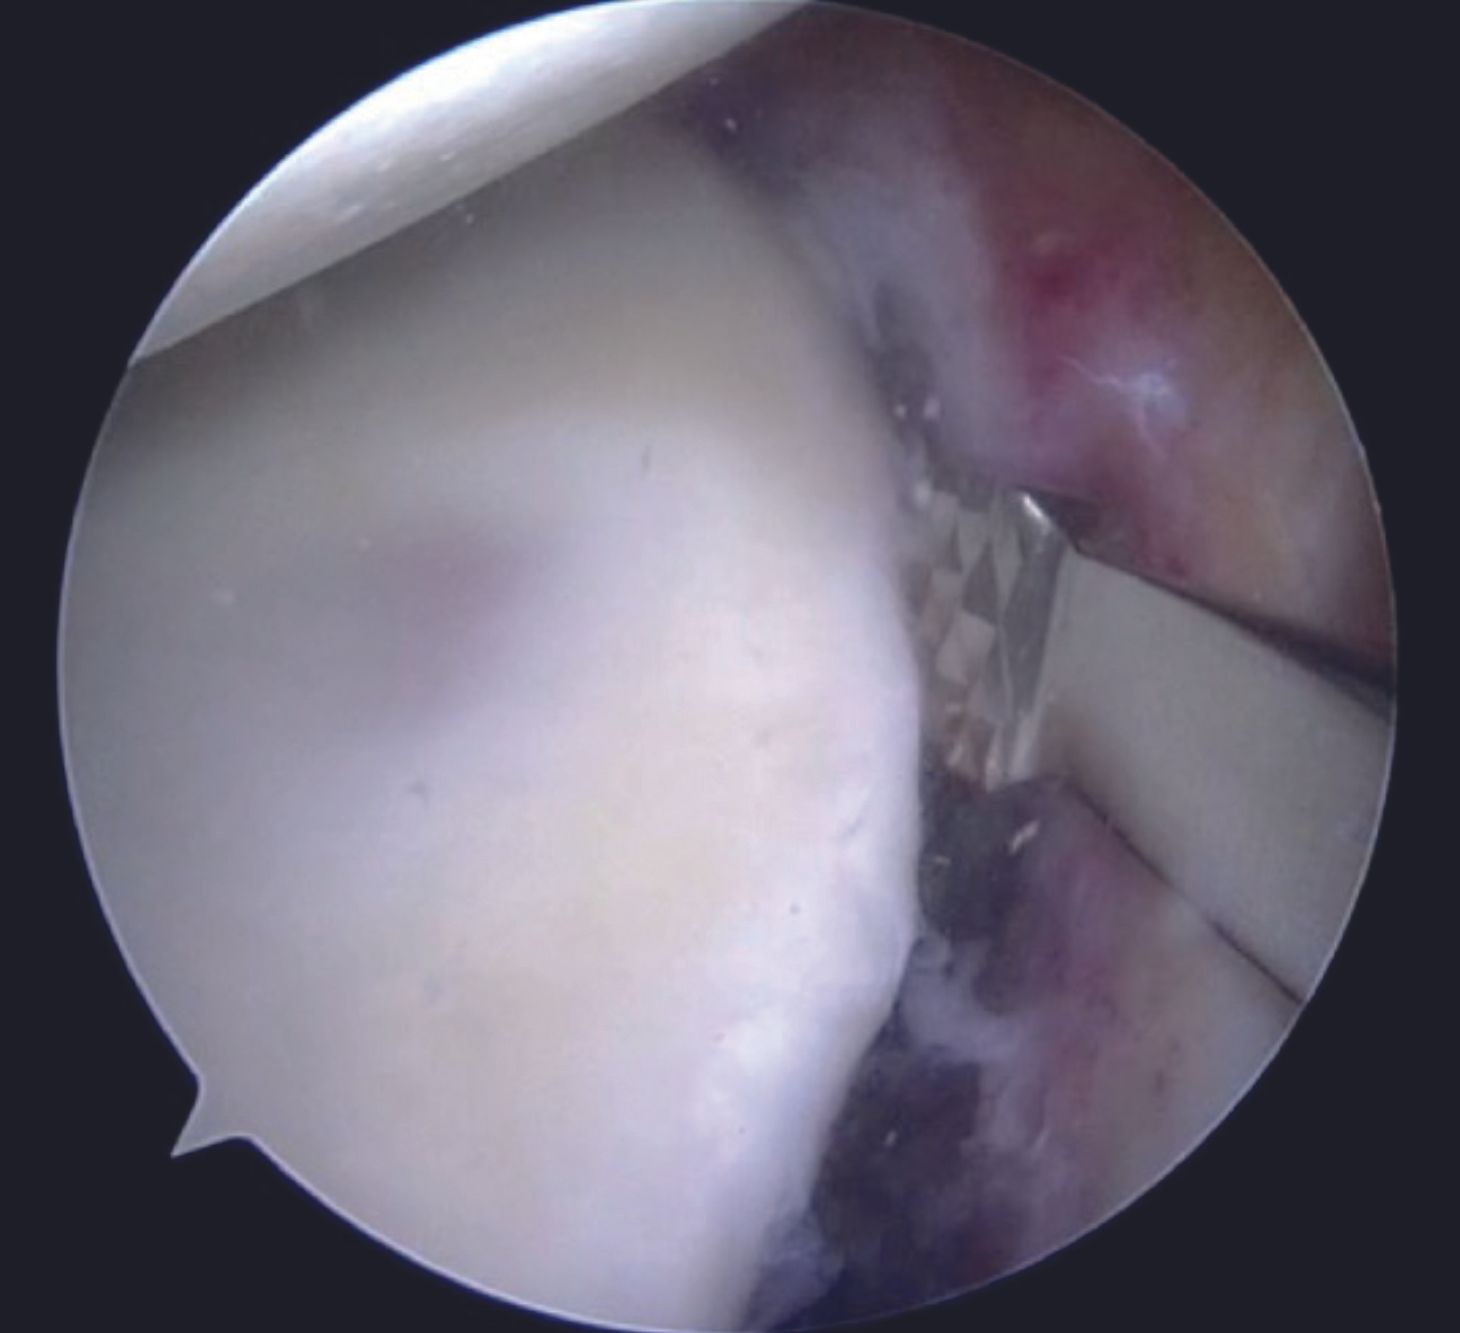

For an isolated Bankart lesion, 3 anchors are usually sufficient. Our preferred choice for the anchor is 1.8mm all-suture anchor as the affected patients are young and thus possess a good quality of the subchondral bone. Advantages of all-suture anchors such as absence of metal implants, no interference with post-operative imaging, easier revision, are well known. Anchor with a tape is preferable to avoid cut-through through the labral tissue. Inferior most anchor is placed first at 5-5.30 O'clock position after drilling a hole using a sleeve through the AI portal (Figure 9). After tapping the anchor in, it is important to pull the tapes so that the anchor bunches up beneath the subchondral bone (Figure 10). Free passage of the tapes is ensured.

One of the tapes is then retrieved through the posterior portal with a tape retriever (Figure 11) and then shuttled through the labral tissue using a suture passer device (Figure 12,13).

A grasper can be utilized for holding the labral tissue in order to allow easy passage of the suture passer device. With both the tapes in the AI portal, a sliding Duncan loop knot is first tied (Figure 14), followed by at least three half hitches.